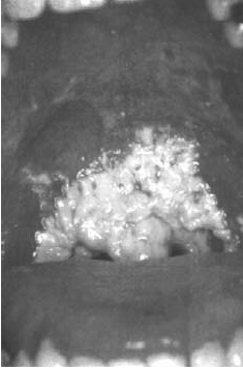

1.1.1 Candidiosi

buca orale

1.1 Candidosi

Infezione

da fungo „tipo lievito¾ (candida albicans) del cavo orale, lingua, vulva,

vagina e glande specialmente in uno stato debole del sistema immunitario.

Sintomi:

strato biancastro, perdite biancastre femminili (leucorrea), prurito, caduta

epidermide/mucosa, emorragie.